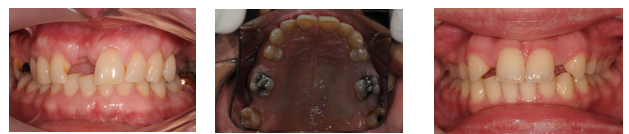

What is a conventional fixed-fixed bridge?

A fixed prosthesis where the pontic is supported by two abutments, one on each side.

conventional prep of abutment teeth: conventional crown

What are conventional cantilever bridges?

Bridges where the pontic is retained by a conventional crown, inlay, or onlay.

retention coming from 1 side only & conventional crown prep of that 1 abutment tooth